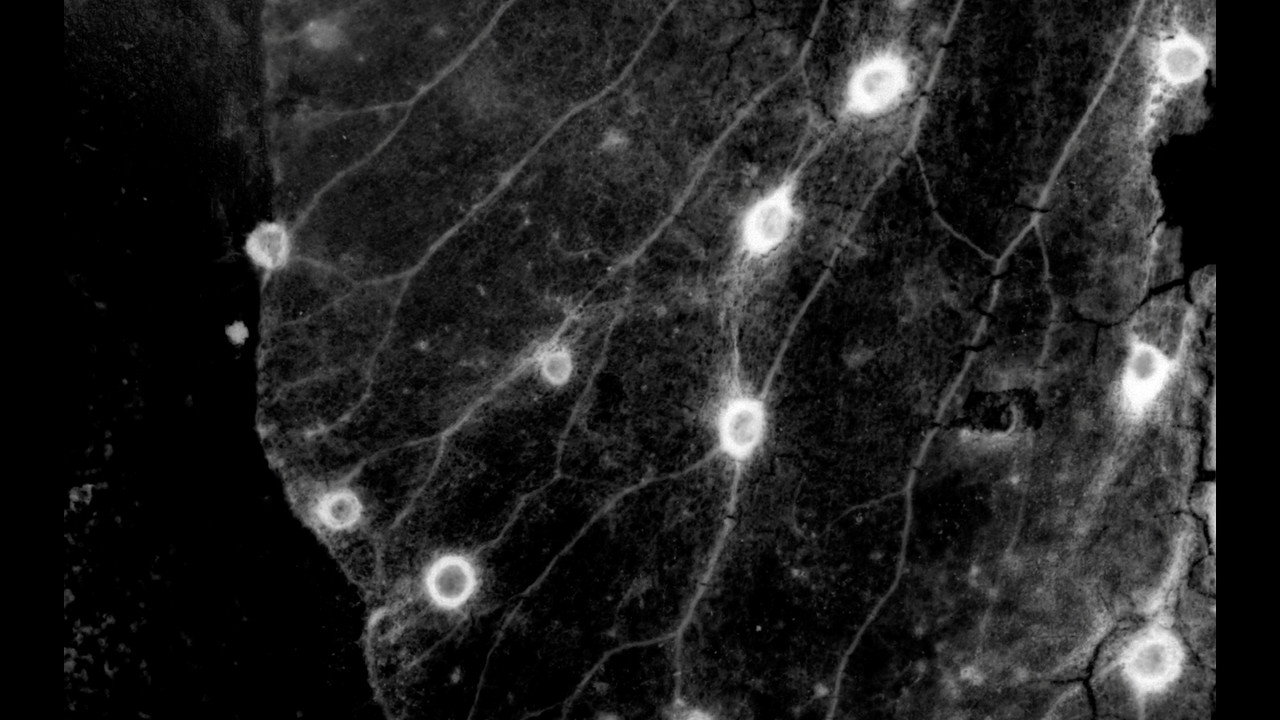

"Emotional memories that had formed the ambiguous boundaries between reality and fantasy began to divide exactly in two, and at the same time there was no emotion left on either side of reality and fantasy." Chang Gyeong is the name of a palace in central Seoul - a palace that was turned into a zoo by the occupying Japanese.